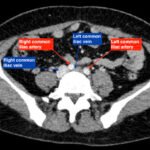

May-Thurner syndrome (MTS) is most commonly caused by the compression of the left iliac vein by the right iliac artery against the lumbar spine, which leads to the development of a partial or occlusive deep venous thrombosis (DVT).1 Diagnosis begins with a duplex ultrasound of the lower extremities to evaluate for a femoropopliteal thrombus, and in high-risk patients where a more proximal DVT is suspected and the DVT ultrasound is negative, a computed tomography venogram (CTV) or magnetic resonance venogram (MRV) is performed.1,3 In this case report, a patient presented to the emergency department (ED) with two days of left lower extremity pain and swelling. Initial lower extremity DVT ultrasound was negative, so a CTV was ordered and revealed a thrombus in the left common iliac vein with overlying compression by the right common iliac artery, suggesting the diagnosis of May-Thurner syndrome (Figure 1). Afterwards, a point-of-care ultrasound (POCUS) was performed at bedside to evaluate the caval and iliac arteries and the findings were consistent with the CTV (Figure 2, 3, 4). If the POCUS was performed prior to the CTV, the patient may have been spared the radiation exposure from CT, as well as the risks of intravenous (IV) contrast required for a venogram. Therefore, in high risk patients in whom a negative DVT ultrasound will prompt advanced imaging with CTV or MRV, I propose the addition of a lower abdominal ultrasound using a curvilinear probe to assess the caval and iliac arteries prior to obtaining a CTV or MRV.